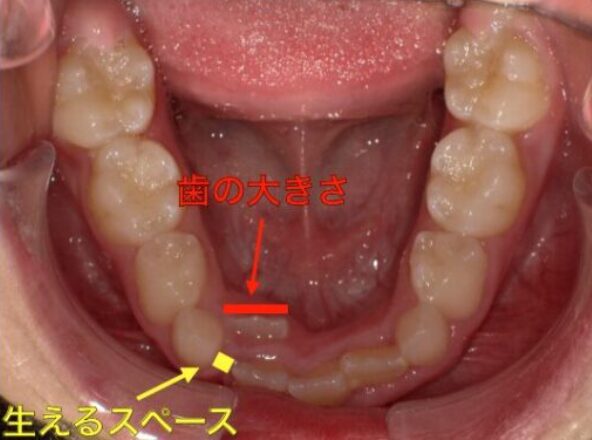

当院の小児矯正では『マイオブレースシステム』を使用し

マウスピースと口腔および姿勢のトレーニング(アクティビティ)の両面から

お子さんの歯並びが悪くなる原因を改善する治療を行っています。